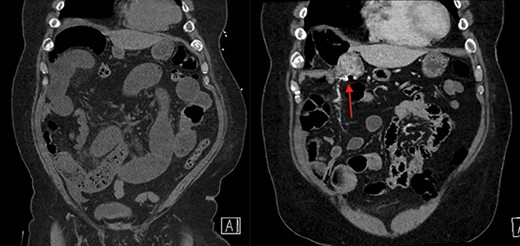

On the left is the initial CT scan non-contrast demonstrating dilated small bowel loops and a transition point in the right lower quadrant. On the right is the CT angiography (CTA), performed a week later, showing a mass and pill cam in the right upper quadrant.

The patient is a 69-year-old male with a past medical history of hypertension, chronic kidney disease, chronic obstructive pulmonary disease, right renal cancer status post-laparoscopic nephrectomy in 2016 (pathology showed renal cell carcinoma with invasion into the adrenal gland, Fuhrman nuclear grade 3–4, pT4 pN0, Stage IV) who presented to the emergency room (ER) with abdominal pain. The patient recently underwent an esophagogastroduodenoscopy and a colonoscopy the week prior as a workup for anemia, which were unremarkable. Since then, he started having intermittent abdominal pain and bloating. The CT abdomen and pelvis without contrast in the ER showed multiple dilated small bowel loops with a transition point in the right lower quadrant (Figs 1 and 2). Due to his history of previous abdominal surgery, this was diagnosed as a small bowel obstruction secondary to adhesions. He was initially managed with a nasogastric tube and gastrografin study. On hospital Day 1, he had minimal output from his nasogastric tube and started to have bowel movements; therefore, his nasogastric tube was removed and he was started on a liquid diet. His diet was advanced, and on hospital Day 2, the patient was discharged.

The next week, unbeknownst to his Gastroenterologist about his recent small bowel obstruction admission, he then proceeded with a capsule endoscopy study to assess for other causes of his anemia. He tolerated the pre-operative bowel preparation without issues. After swallowing the capsule, he subsequently had bloody bowel movements. He then went to the ER and found to have a hemoglobin of 7.1, which was decreased from his prior week’s hospitalization, 8.4. A CT angiography (CTA) abdomen and pelvis was then performed that showed a 4 × 6 × 4.1 cm mass in the right upper quadrant with the capsule endoscopy at the level of the mass (Figs 1 and 2). The images from the capsule were unremarkable. On review of his imaging with radiology, it appeared that this mass was not apparent without IV contrast on his previous CT scan a week prior. In addition, a prior CT abdomen pelvis with IV contrast 10 months ago was negative for a small bowel mass. A repeat abdominal and pelvis CT with oral and IV contrast was done for confirmation. This re-demonstrated the 6 cm mass with the capsule stuck proximal to it; therefore, we performed a diagnostic laparoscopy.